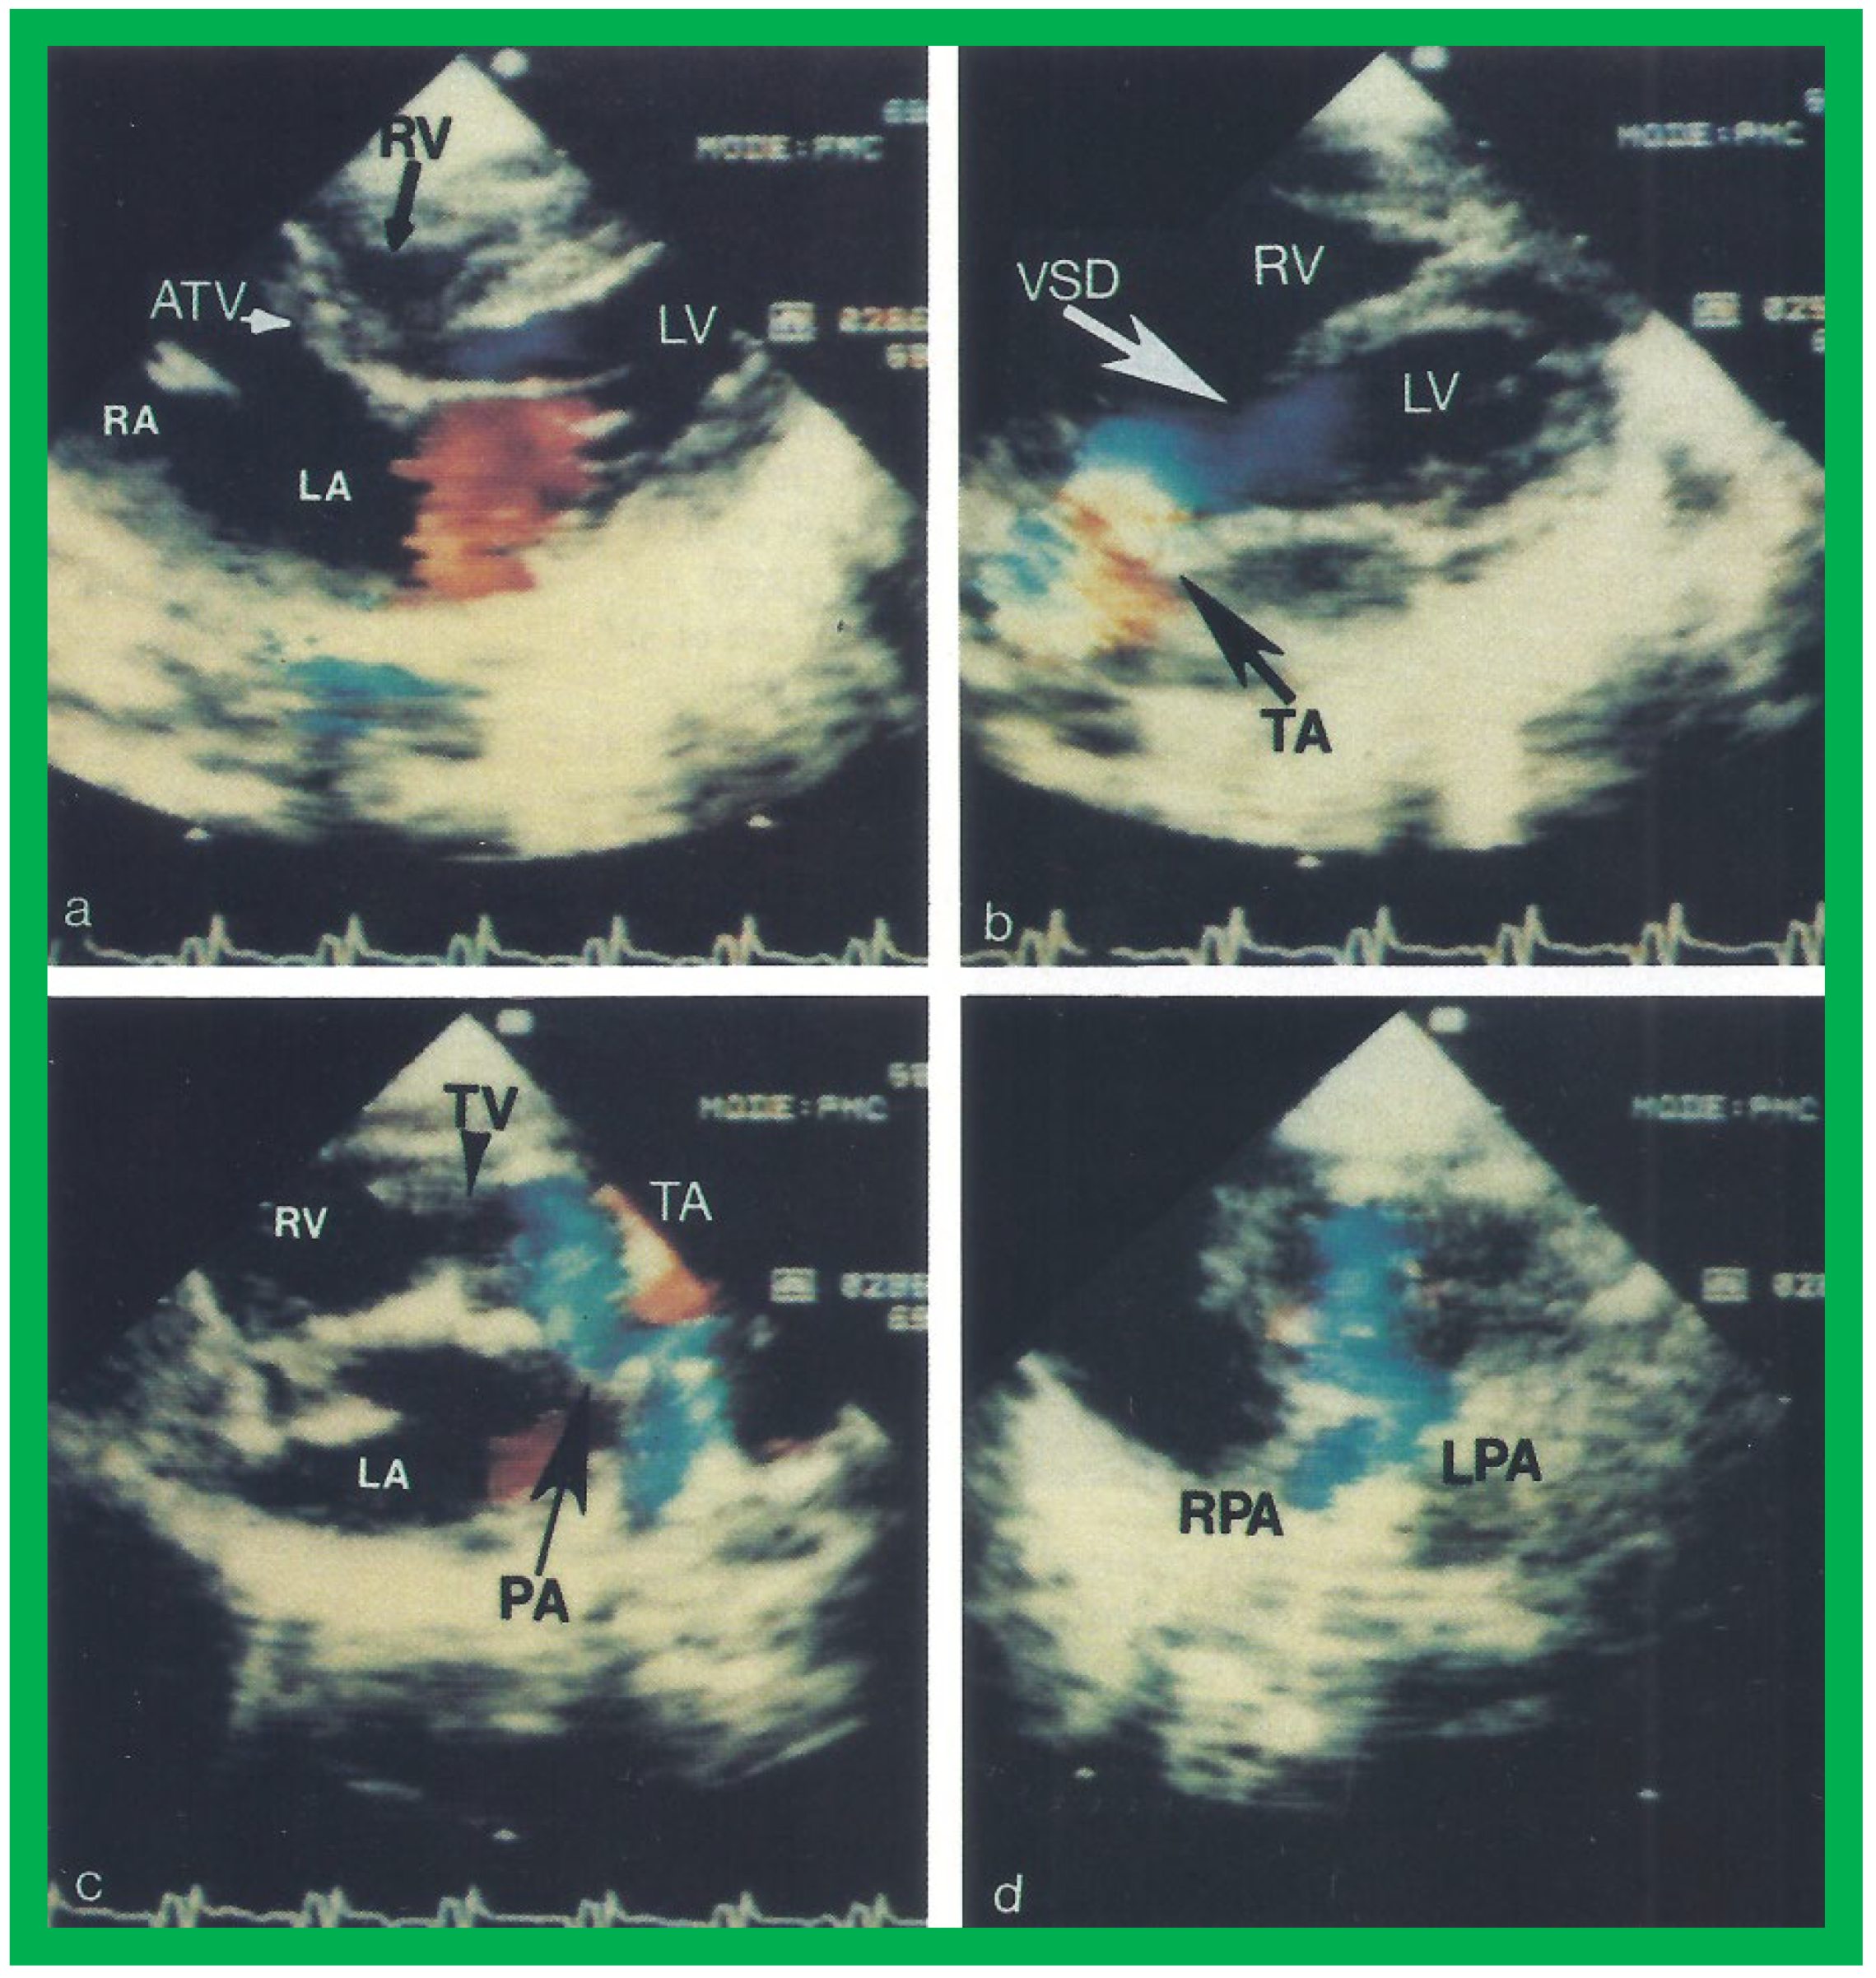

The relationship of the great arteries is examined next in order to classify them into various types, as mentioned above. The relationship of the great arteries (Figure 2, top) is established by following the vessels arising from the ventricles until the pulmonary artery (PA) bifurcation or aortic arch. In Type I patients with normally related great arteries, the aorta arises from the LV (Figure 5) and in Type II patients with transposition of the great arteries, the PA arises from the LV (Figure 6; Figure 7). In Type II patients, the blood vessel arising from the LV should be traced to demonstrate its branching into the right and left PAs (Figure 6; Figure 7). In Type III patients, it may be a little more difficult to assign the great artery relationship and, sometimes, other imaging studies, including angiography, may be needed to define the great artery relationship. In Type IV with truncus arteriosus, the limited data suggest that this can be performed by echocardiography (Figure 8; Figure 15). In the example shown [22], the atretic tricuspid valve (Figure 8a and Figure 9a), VSD (Figure 8b and Figure 9b), hypoplastic RV (Figure 9a), single vessel (truncus) arising from the heart (Figure 8c,d, and Figure 9c,d), and origin of the PA and its division into branch PAs (Figure 8d, and Figure 9c,d) were demonstrated.

Figure 8. Two dimensional echocardiographic video frames demonstrating (a) an atretic tricuspid valve (ATV) between the right atrium (RA) and right ventricle (RV), (b) a large subtruncal ventricular septal defect (VSD), (c) thickened and somewhat domed truncal valve (TV) leaflets, and (d) the origin of the pulmonary artery (PA) from the posterior aspect of the truncus arteriosus (TA). LA, left atrium; LV, left ventricle. Reproduced from Rao PS, et al. Am Heart J 1991;122:829–835 [22].

Figure 9. Video frames from a two dimensional echocardiographic and color Doppler study demonstrating (a) an atretic tricuspid valve (ATV) between the right atrium (RA) and right ventricle (RV), and blood flow from the left atrium (LA) into the left ventricle (LV) across the mitral valve. The RV (arrow) is very small and hypoplastic. (b) LV and RV with a large ventricular septal defect (VSD) below the truncus arteriosus (TA). Turbulent flow across the truncal valve suggests truncal valve stenosis. (c) The origin of the pulmonary artery (PA) from the TA by color flow (arrow), and (d) the division into right (RPA) and left (LPA) pulmonary arteries from the PA in a short-axis view. TV, truncal valve leaflets. Reproduced from Rao PS, et al. Am Heart J 1991;122:829–835 [22].